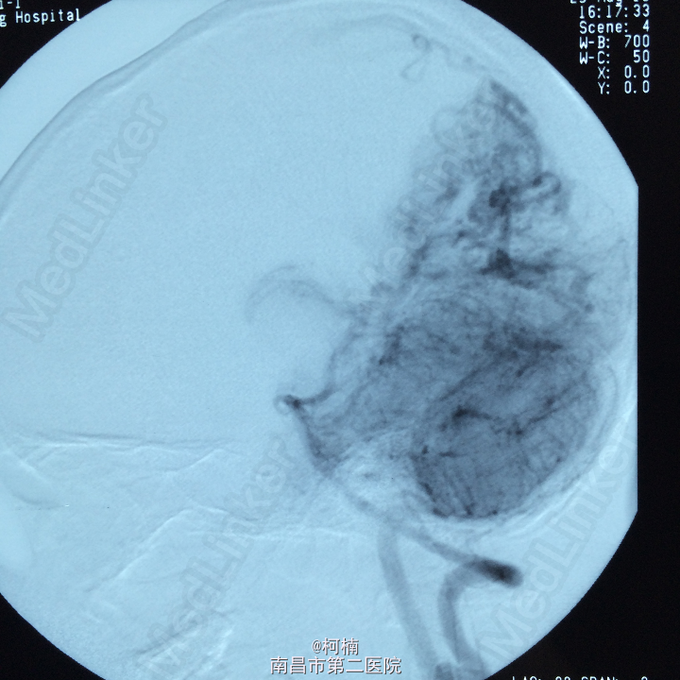

主诉:头痛伴呕吐2天,意识障碍1天 病史:患者于2天前运动后出现头晕头痛,为爆炸样头痛,程度较重,伴呕吐多次,呕吐物均为为内容物,伴四肢乏力,予休息处理。次日清晨患者出现头痛加重,伴呕吐,甚至模糊,呈嗜睡状态,呼之能应,遂急诊送入当地ICU治疗,查头部CT示:蛛网膜下腔出血,予脱水、止血对症治疗后患者症状无明显缓解。转入我院进一步治疗。

查体:神志朦胧,颈抵抗,右侧肢体及躯干深感觉减退,左侧正常。 辅助检查:复查CT提示左侧额叶出血破入脑室系统

诊断:脑动静脉畸形 处理:予急诊行DSA检查,提示脑动静脉畸形,予行血管内栓栓塞治疗